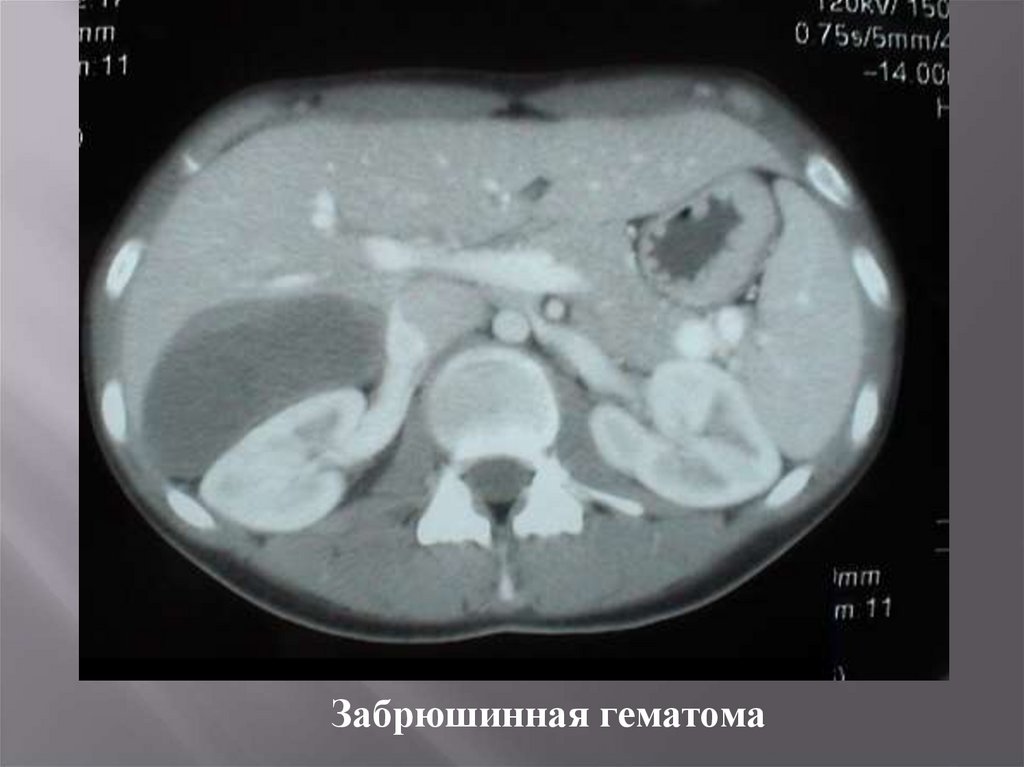

28.

КТ при закрытой травме правой почки после падения на бок.

Диагностика точная, быстрая, но дорогая.

29.

Забрюшинная гематома